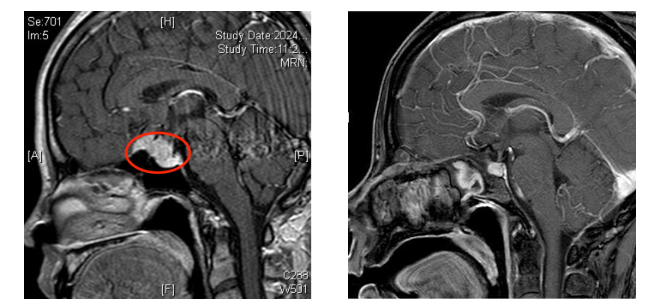

经过颅脑磁共振平扫+增强后,发现鞍上及前颅窝底占位性病变,考虑鞍结节脑膜瘤。通常处理方式为开颅手术切除,但张女士及家属对常规开颅手术抱有恐惧心理,且开颅手术对患者发际外的容貌有一定的影响。

经过周密的手术计划,凭借高超的手术技巧,王开宇主任医师团队在未伤及颅内动脉和视神经的前提下,利用神经内镜技术,精准地将瘤体切除,成功完成了手术。术后,张女士双眼视力一天天好转,较术前得到了很大改善。目前张女士已康复出院,没有出现颅内感染和脑脊液等并发症,垂体功能也完全正常。

▲术前术后影像学对比,可见肿瘤完全切除